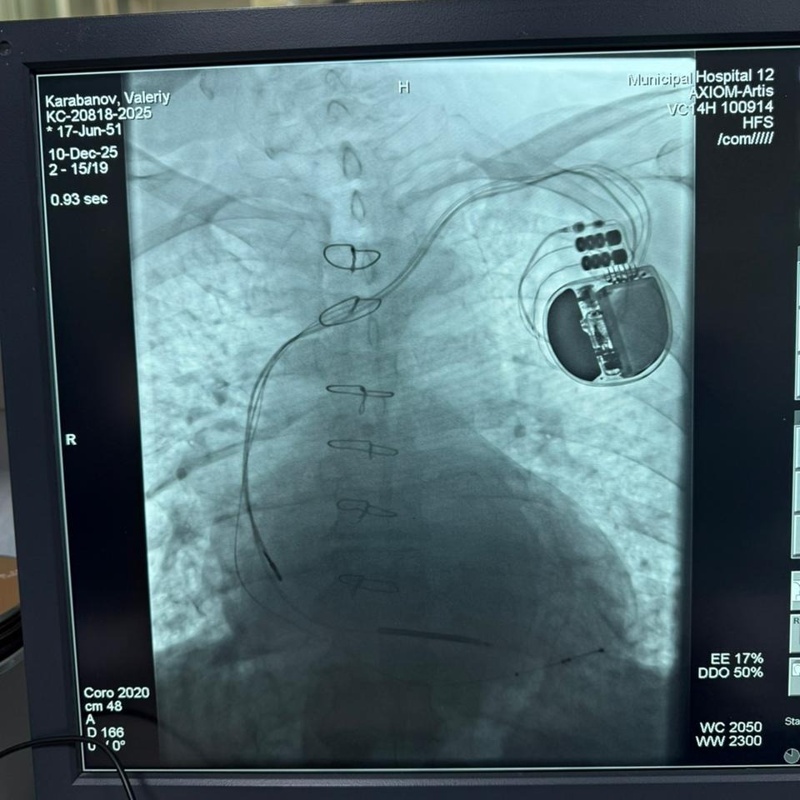

Cardiologists at the Central City Clinical Hospital in Almaty have carried out the hospital’s first procedure to implant an implantable cardioverter-defibrillator (ICD), a device used to protect patients from dangerous heart rhythm disorders and sudden cardiac arrest, Qazinform News Agency reports.

The surgery was performed on a 58-year-old man suffering from severe cardiovascular disease accompanied by advanced heart failure. Tests showed a critically low ejection fraction of 27-28%, far below the normal level of 55-70%, indicating a high risk of life-threatening arrhythmias.

“The ICD implantation was performed under local anesthesia. The device was inserted into the subclavian region, and the electrodes were passed through the blood vessels into the heart chambers. "If a dangerous rhythm disturbance occurs, the device automatically recognizes the problem and responds immediately, restoring normal heart function at the critical moment when the chances of successful rhythm restoration are highest," explained Gani Tulepbergenov, an arrhythmologist at the Central City Clinical Hospital.